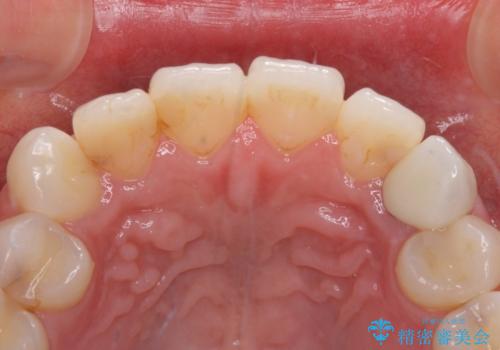

土台の金属を除去してファイバーコアによる土台植立を行い、オールセラミッククラウンにて補綴することとしました。

前歯1本の治療では、オールセラミッククラウンといえども周囲と調和しなければ自然な仕上がりにはなりません。

今回は既製の色調のセラミックを選択されましたが、もっと色合いにこだわりたい場合には、オーダーメイドタイプのセラミッククラウンをご選択いただいています。